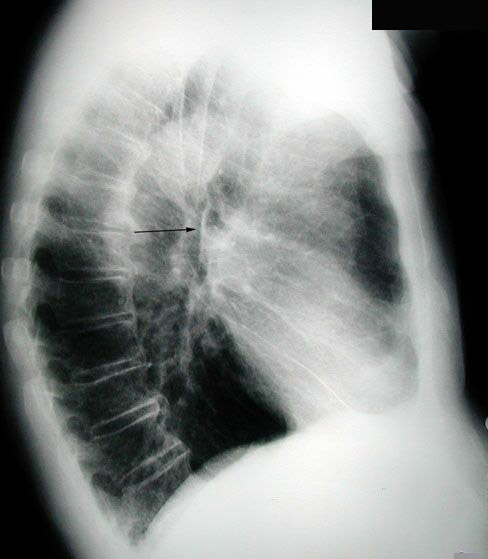

Thickened Intermediate Bronchus This patient presented with hemoptysis. The PA view is normal. However, there was a lesion in the intermediate bronchus found on bronchoscopy. This was suspected due to the thickened intermediate bronchus. This is not a reliable sign, unless it is unquestionably thickened. This is a case of bronchogenic carcinoma. Normal thickness: